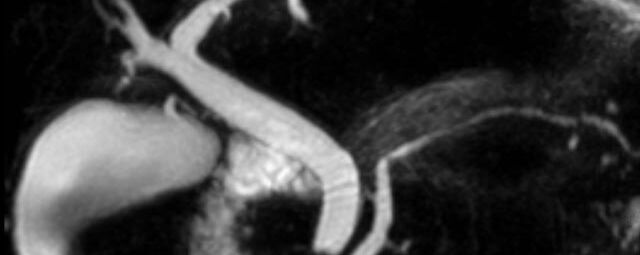

MRT - Herzens

MR-Angiographie zur Erfassung und Verlaufskontrolle von Aneurysmen der Aorta thorakalis und ihrer Gefäßabgänge